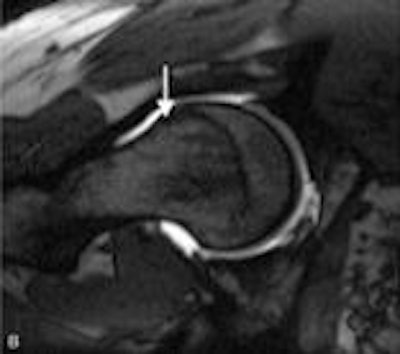

| An apparently normal lateral radiograph of the hip (above) in a patient with femoroacetabular impingement. MRI (below) of the same patient shows significant femoral head-neck offset abnormality. The arrow indicates an anterolateral head-neck junction cam impingement bump. Images courtesy of AAOS. |

Panelist Kawan Rakhra, MD, from Ottawa Hospital and the University of Ottawa, explained that dGEMRIC can detect changes in glycosaminoglycan in the cartilage of a patient with arthritis. The cartilage looks normal on x-rays and standard MR images, but dGEMRIC can determine that the cartilage is biochemically abnormal.

In patients with obvious symptoms of femoroacetabular impingement (FAI) for whom radiographs and MRI scans are normal, dGEMRIC and other new imaging techniques may be useful.